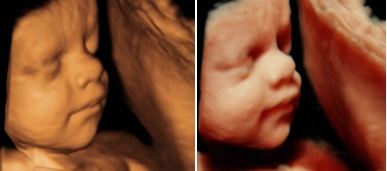

Täiendatud 3D/4D programm võimaldab töödelda kolmemõõtmelist loote kujutist andes sellele võimalikult realistiku loote välimuse. Selle programmiga on võimalik valgustada loote nägu erinevate nurkade alt, parandades ruumilist kujutist ja tuues erinevate varjude abil paremini esile muidu varju jäävad täpseks diagnoosimiseks vajalikud olulised pisidetailid. HDlive pilditehnika aitab ka perel paremini mõista ultraheliaparaadi ekraanil visualiseeritavat loote kujutist, muutes kõhubeebi palju armsamaks kui eelneva ultraheliaparaadi tarkvara puhul.

Pilt (klikkides video) Loode 30. rasedusnädalal. Kasutusel HDLive pilditehnika programm ja kõhukaudne unikaalne maatriksandur RM6C. Dr. Marek Šois